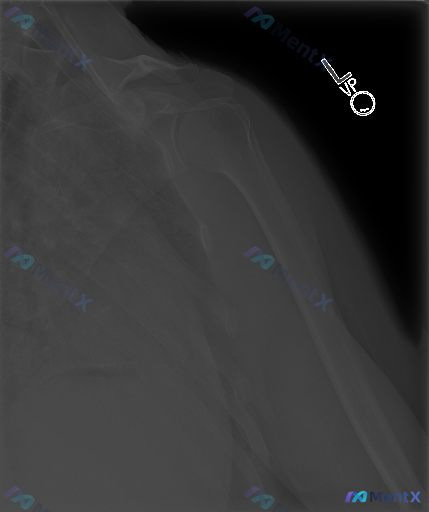

影像科结论写得很明确:左肩侧位(Scapular Y-view)X光片未见明确的急性骨折、脱位或明显的关节结构异常,盂肱关节对位良好,骨质也没有明显的退行性改变。

连肩袖附着区的钙化、软组织肿胀都没看到。

但如果临床场景是:患者有明确的外伤史,或者持续左肩疼痛、活动受限,这份“完全正常”的片子应该怎么解读?